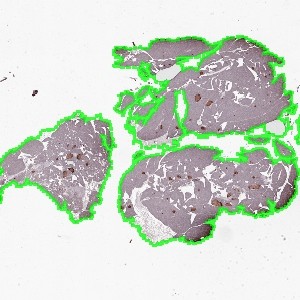

Figure 1

Whole slide image of pancreas tissue.

The same image as in FIGURE 1 after automated tissue outlining by the auxiliary APP Mouse Pancreas, Beta- and Non-beta Cell Area – 01 Tissue detect.